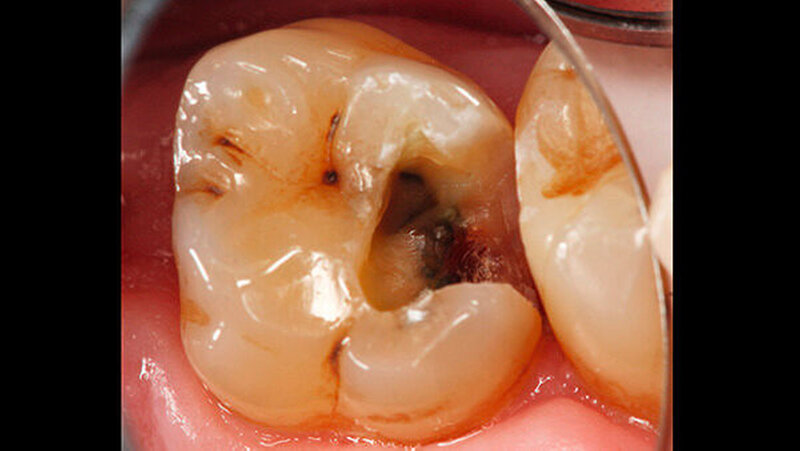

Die Sensibilitätsprüfung des Zahnes 26 auf Kälte mit CO

2

-Schnee war positiv. Die Behandlung wurde auf Wunsch des Patienten ohne Lokalanästhesie durchgeführt. Vor der Präparation erfolgte das Anlegen von Kofferdam an den Zähnen 24 bis 27. Zunächst wurde mit rotierenden Diamantschleifern unter Wasserkühlung von okklusal ein Zugang zum Defekt geschaffen. Der distale Kavitätenbereich wurde mit oszillierenden Instrumenten präpariert (SonicFlex, KaVo) (Abbildung 2). Dabei wurde die Kavität so zierlich wie möglich gestaltet.